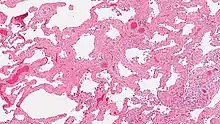

Smoking-related interstitial fibrosis (SRIF)

Smoking-related interstitial fibrosis (SRIF) is an abnormality in the lungs characterized by excessive collagen deposition within the walls of the air sacs (interstitial fibrosis). This abnormality can be seen with a microscope and diagnosed by pathologists. It is caused by cigarette smoking.[1][2]

The defining feature of smoking-related interstitial fibrosis is a distinctive/unique type of fibrosis characterized by "ropey" collagen bundles within the walls of the air sacs (alveoli), almost always in association with other smoking-related abnormalities such as pigmented macrophages and emphysema.[6]